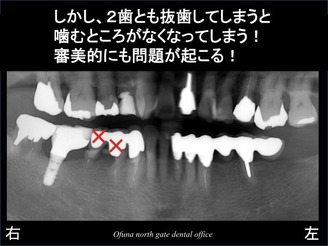

ダメになった部分を拡大してみましょう!

見る人が見れば明らかに分かるような 悪い状態です。

次に問題となったのが、抜歯後の治療の進め方です。

2歯とも抜歯してしまうと 当然のことながら 欠損してしまいます。